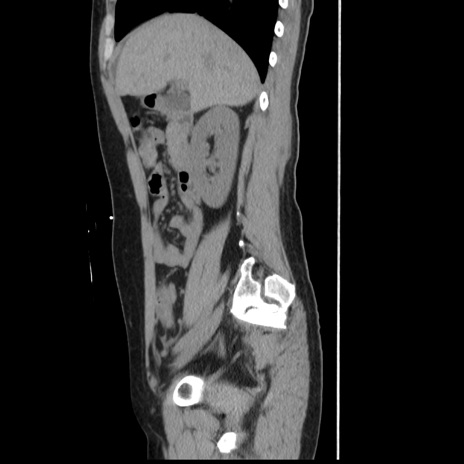

症例10(矢状断像)

【症例】 50歳代女性

【主訴】 腹痛

【現病歴】前日生レバーを食べた。今朝に排便あり。 昼前に突然発症の腹痛を生じ、当院救急外来を受診した。

【既往歴】 子宮筋腫にてで子宮全摘後

【身体所見】 意識清明、腹部:平坦、軟、下腹部やや左を中心に圧痛・反跳痛あり、筋性防御あり

【データ】WBC 7800、CRP 0.07